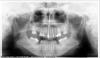

leya333 Опубликовано 26 января, 2013 Автор Поделиться Опубликовано 26 января, 2013 Принципиальной разницы между имплантатами нет, разместите тут ортопантомограмму, кт не все будут качать Да, извините, вот орто. Ссылка на комментарий

Mane Опубликовано 28 января, 2013 Поделиться Опубликовано 28 января, 2013 Мне первый нравится . Вы знаете иногда такой бред услышишь что стыдно за врачей становится. Откровеннаяя ересь это сделать синус-лифтинг там где он не нужен так еще и без имплантатов. Это я конкретно про ваш случай. Ваша четверка не помеха. Решать ее можно и после имплантации. По поводу выбора имплантатов. Важен не имплантат. Тут подойдет любой. Доктора (оба) лукавят. Все хотят кушать. Мне из этх двух систем больше симпотизирует анкилос. Но это в общем, а не потому что он лучше для вас или в вашей ситуации подходит больше. Анкилось конструктивно на шаг впереди альфа био. Но еще раз повторю вам подойдут любые. Лучше доктора "золотые руки", чем имплантаты по круче у "слесаря". Насчет синяков- не согласен. Скорее их не будет чем будут. Объем операции не так велик. Про кость- у вас достаточно кости для установки имплантата длиной 8 мм. Это я на глаз определил. Стандартом же считается длина 10 мм. То есть та длина которая наиболее популярна и которая обеспечивает работу имплантата всю жизнь. Соответственно если б я вам планировал операцию я б все таки сделал вам закрытый синус литинг в момент установки имплантатов путем перемещения вашего же костного дна без добавления материалов и установил бы импланты длиной 10 мм. 1 Ссылка на комментарий

Bier Опубликовано 28 января, 2013 Поделиться Опубликовано 28 января, 2013 справа и 10мм имплантат войдет, если не исправлять положение восьмерки и ставить только 1 имплантат. Слева тоже похоже войдет, ну может немного пазуху приподнимет. Я бы Альфу поставил, ей проще дно пазухи поднять. Ссылка на комментарий